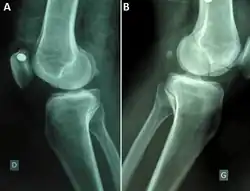

Medio-lateralradiographsof knees joint showing a bilateral Hoffa fracture of the medial femoral condyle and fracture suspicion of left tibia plateau. (A) right knee; (B) left knee.[1] |

A Hoffa fracture is an intra-articular supracondylar distal femoral fracture, characterized by a fracture in the coronal plane.[1]